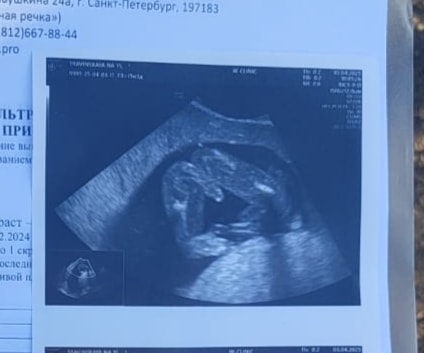

у меня на 16й неделе был вот такой снимок. Врач сказал что мальчик. Потом на скрининге подтвердили